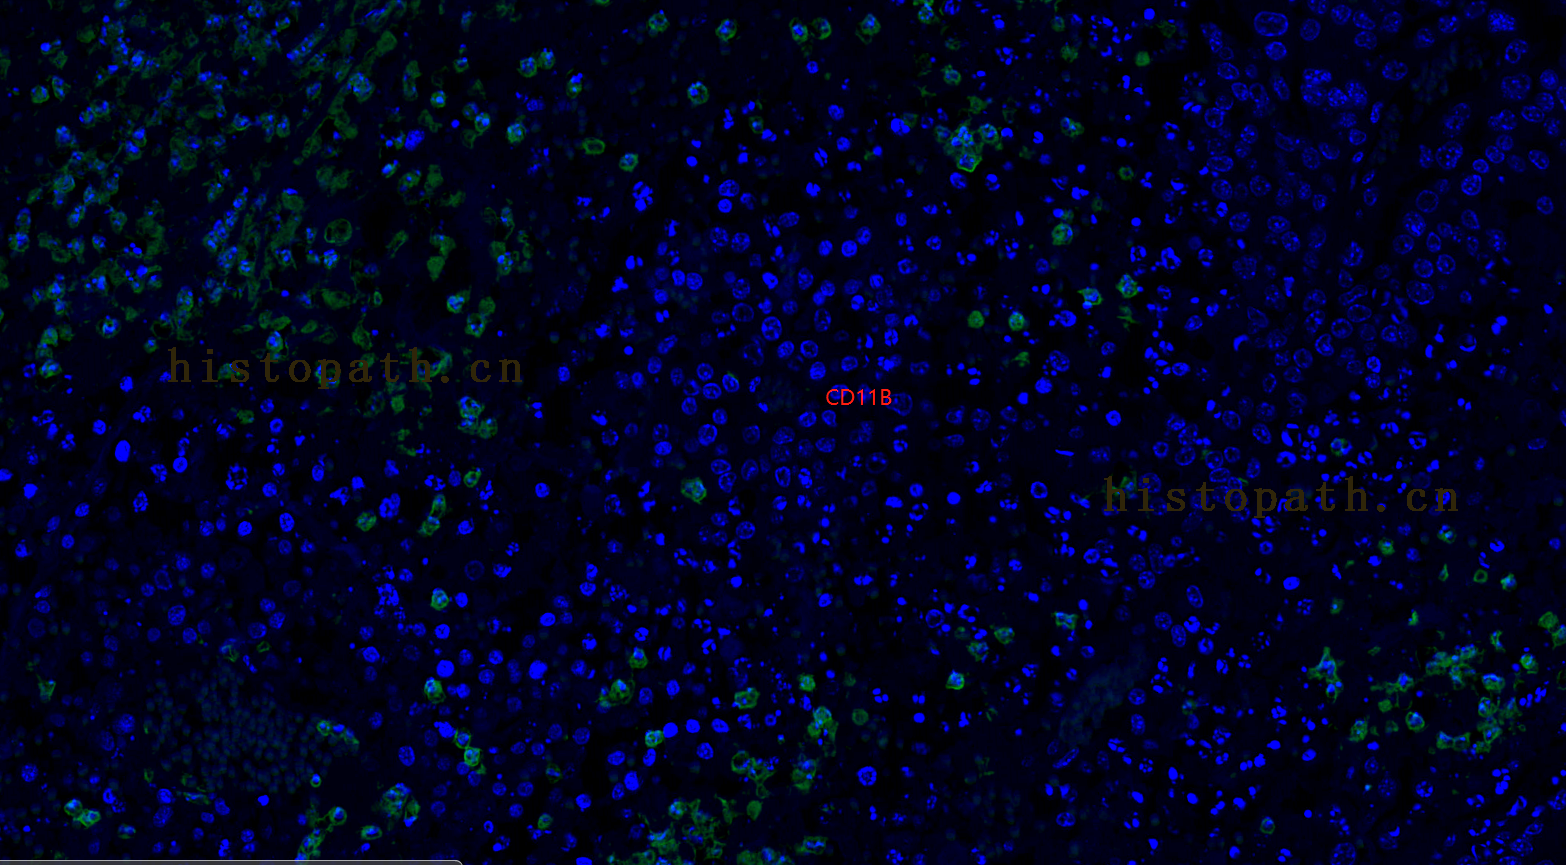

二、免疫荧光(双标)

免疫荧光双重标记即利用抗原抗体特异性结合原理,在同一张切片上两个抗原进行同时标记,从而实现定位,定性,半定量的分析。1、石蜡切片脱蜡至水:依次将切片放入二甲苯Ⅰ15min-二甲苯Ⅱ15min-无水乙醇Ⅰ5min-无水乙醇Ⅱ5min-85%酒精5min-75%酒精5min-蒸馏水洗。

10、镜检拍照:切片置于扫描仪下采集图像。(DAPI紫外激发波长330-380nm,发射波长420nm,发蓝光;FITC激发波长465-495nm,发射波长515-555 nm,发绿光;CY3激发波长510-560,发射波长590nm,发红光. CY5激发波长 608-648nm, 发射波长672-712。 DAPI染出来的细胞核在紫外的激发下为蓝色,阳性表达为相应荧光素标记的红光,绿光 。